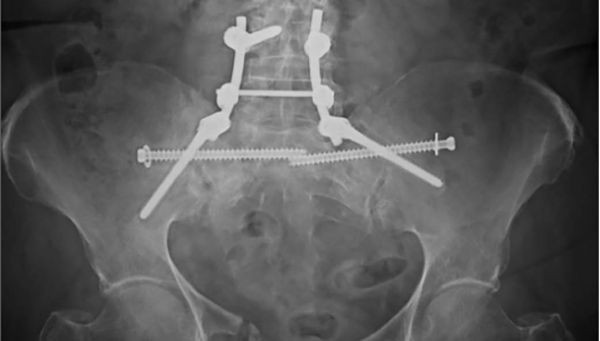

Abb. 4 (oben) : postoperative konventionell radiologische Kontrolle nach percutaner horizontaler Stabilisierung des hinteren Beckenrings beidseits mit Fixateur interne und iliosacraler Schrauben („iliosacrales bridging“) in anterior-posteriorer Projektion

Abb. 4: postoperative konventionell radiologische Kontrolle nach percutaner horizontaler Stabilisierung des hinteren Beckenrings beidseits mit Fixateur interne und iliosacraler Schrauben („iliosacrales bridging“) in anterior-posteriorer Projektion

In der Folge wurden auch Ergebnisse nach Zementaugmentation dieser Fixateuranordnung bei instabilen Fragilitätsfrakturen beschrieben [18]. Es besteht als Modifikation dieser Methode zudem die Möglichkeit, den horizontalen Fixateur zur Versorgung unilateraler Becken-B-Verletzungen einzusetzen. Dies gelingt durch eine Verkürzung der Fixateuranordnung und Platzierung einer Schraube auf der unverletzten Seite des Os sacrum in Höhe des S1-Pedikels. Über das Instrumentarium des Fixateurs besteht zusätzlich die Möglichkeit einer gewissen Kompression im Frakturbereich. Zudem kann sowohl mono- als auch bilateral durch eine ergänzende transiliosakrale Verschraubung („iliosacrales bridging“) [Abb. 3 und 4] die Stabilität weiter erhöht werden [17], wobei durch die horizontal hintereinander liegenden Implantate (iliosacrale Schraube + Fixateurquerträger) die Stabilität gegenüber den weiteren beschriebenen Verfahren nochmals deutlich erhöht sein müsste. Bei relativ neuer Osteosynthesetechnik stehen hierzu jedoch vergleichende Studien noch aus. Das „iliosacrale bridging“ zeigt bei einem von Altersstruktur und Verletzungsschweren gemischten Patientenkollektiv gute Ergebnisse.